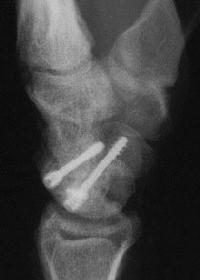

Case 8. Transscaphoid perilunate fracture dislocation...

Click for larger image

Two screws put in dorsally, LT ligament reinforced with a strip of extensor retinaculum left attached to the triquetrium and anchored into the lunate; temporary capitolunate pin.